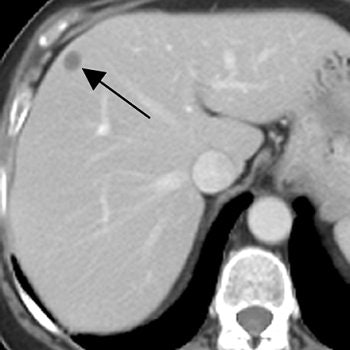

For this retrospective review, more than 5,000 women diagnosed with breast cancer between 2000 and 2003 at Sloan-Kettering were included. All MRI exams were done on 1.5-tesla scanners and the protocol included axial in-phase and opposed-phase T1-weighted gradient-echo images; axial fat-saturated fast spin-echo T2-weighted images; and dynamic multiphase gadolinium-enhanced axial T1-weighted gradient-echo images. CT scans were obtained on scanners with 7.0- to 7.5-mm collimation.

According to the results, 1.4% of the 5,440 women underwent MRI of the abdomen after initial diagnosis of breast cancer. Of those 76 patients, 50% had at least one hepatic lesion that was deemed too small to characterize on CT. The majority of these women (61%) had more than one lesion, including cysts and hemangiomas. In 21% of these patients, no lesion was found on MRI at the site that corresponded to at least one small hepatic lesion found on CT.

| A 71-year-old woman with invasive ductal carcinoma. Above, contrast-enhanced CT shows hepatic lesion (arrow) deemed too small to characterize. Below, contrast-enhanced T1-weighted MR image obtained 13 days after CT shows lesion (large arrow) in CT image is not enhanced, diagnostic of cyst. Lesion (small arrow) in posterior right lobe represents partial volume averaging of another cyst, which was evident in more caudal images (not shown). Patterson SA, Khalil HI, and Panicek DM, "MRI Evaluation of Small Hepatic Lesions in Women with Breast Cancer" (AJR 2006; 187:307-312). |

Overall, only 5% of the hepatic lesions were considered malignant based on the MR study, the authors noted. The majority of lesions was benign or remained indeterminate. "Thus in 95% of the women ... the results of MRI did not alter medical management because therapy is not changed for benign or indeterminate liver lesions.... MRI is not warranted," they concluded.